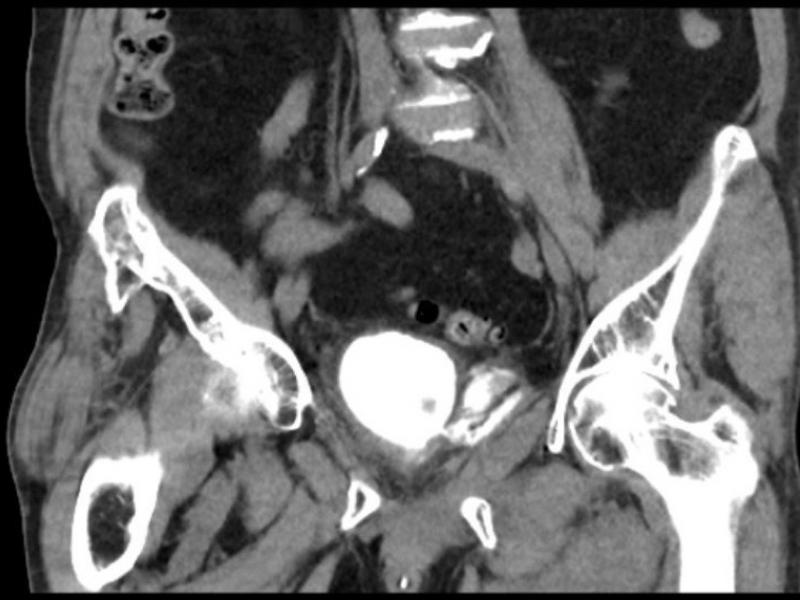

What's the diagnosis?  By Dr. Katie Selman

January 15 2020

A 76 yo female presents after a fall down several stairs